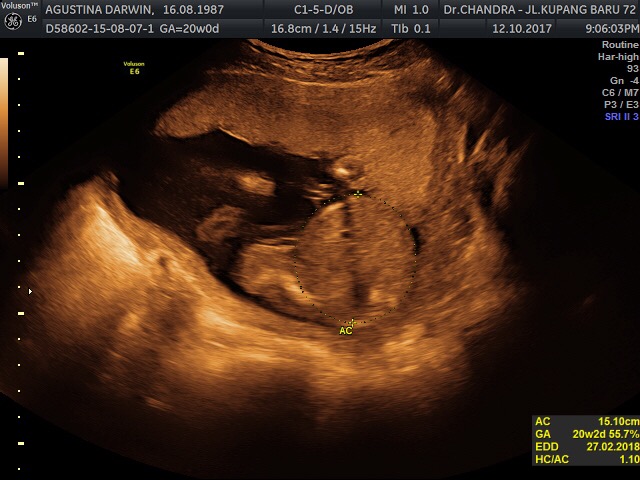

9 Nov 2017 ( 24 weeks )

Hari ini,pas dd berumur 24weeks, kali ini pemeriksaan seperti biasa,antri menunggu giliran.

Setelah itu dr.Chandra mulai mengoleskan gel usg 2dimensi untuk memeriksa keadaan janin di dalam.

Dan langsung ditemui,plasenta / ari2nya melilit di lehernya, tapi untungnya lilitannya hanya 1x, longgar dan tidak erat. Pada usia kehamilan 24w, masih besar kemungkinan janin bisa melepaskan sendiri lilitannya.. tapi tidak menutup kemungkinan,janin bisa terlilit lebih banyak lilitan. Lalu diperiksa aliran darah di tali plasenta tersebut, Puji Tuhan alirannya bagus

Berat dd di 24weeks ini 713g, detak jantung, aliran darah, dan kurva pertumbuhannya semua normal sesuai dengan grafik..